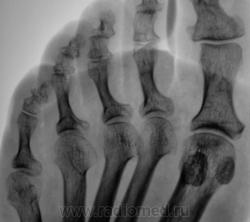

Две стопы - две сестры. Хозяин один.

Неспецифический (остеоартроз)?..

А, может это врожденное?